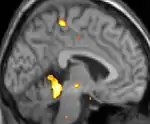

|  |  |  |

| La tomographie par émission de positons (TEP) montre les zones du cerveau étant activées durant la douleur | ||

| La morphométrie voxel par voxel (VBM) montre les différences structurelles des zones du cerveau | ||

Les images par tomographie à émission de positron indiquent les régions du cerveau qui sont activées lors de la douleur, par rapport aux périodes sans douleur. Elles montrent les régions du cerveau qui sont toujours actives durant la douleur en jaune/orange (appelé "matrice-douleur"). La zone au centre (dans les trois vues) est spécifiquement activée uniquement pendant la crise. Les photos sur la ligne du bas (effectuées par VBM) montrent les différences structurelles entre les patients souffrant d'AVF et des personnes saines : seulement une partie de l'hypothalamus est différente[50],[51].